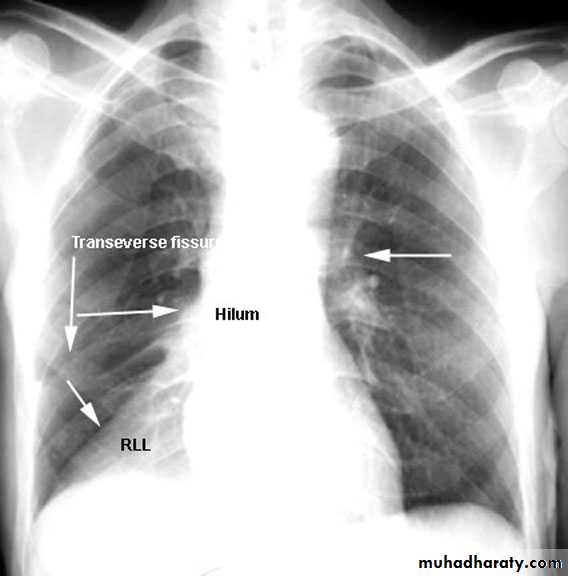

Upper lobe c. Middle lobe c.

rt lower lobe c. Left lower lobe c.